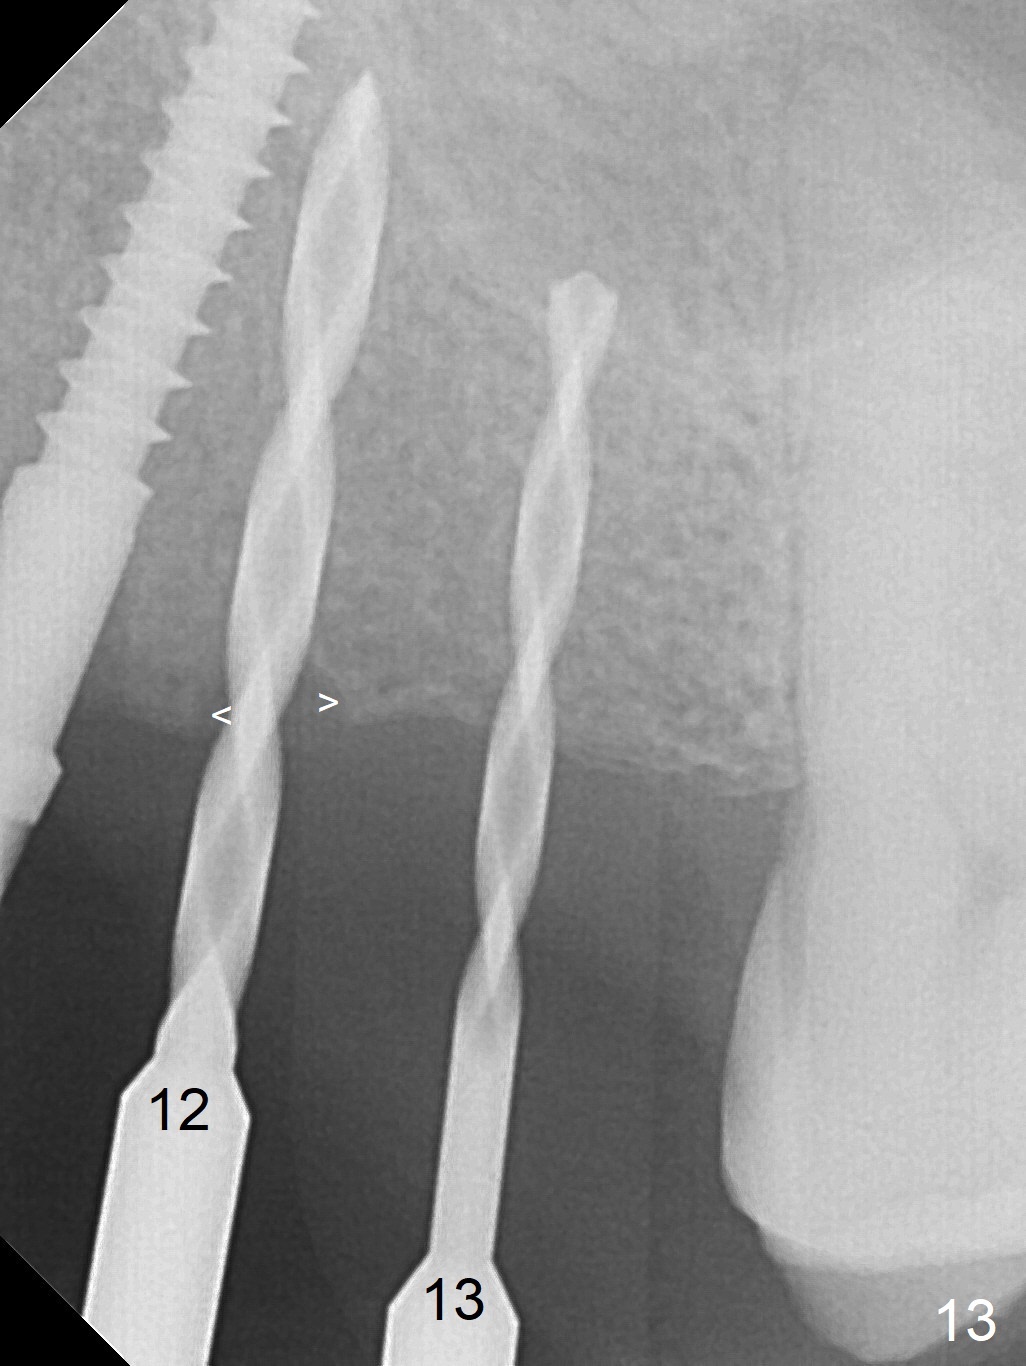

At the sites of #11 and 12, the knife-edged ridge is trimmed prior to initiation of osteotomy (Fig.12,13). With the flattened ridge, it is easy to start osteotomy and control the mesiodistal position. When the position and the trajectory are not correct, they can be changed (Fig.14-16) with 2.5x14(4), 2.5x12(2) and 3x10(2) mm implants placed at #11,12, and 13, respectively. With relatively correct position of each implant, it would be easy to fabricate a splinted 6-unit provisional.